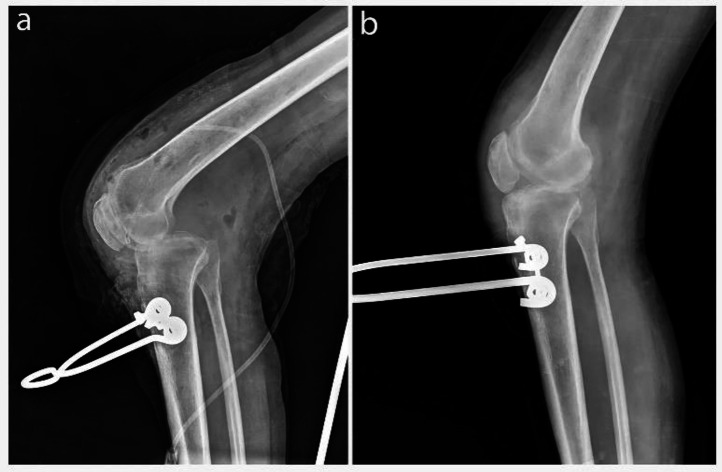

Neglected knee dislocations are rare and challenging orthopedic injuries. We report using a traction pin to treat a neglected knee dislocation and a concurrent infection. Following the primary reduction with extensive soft-tissue release, a proximal tibial traction pin was used to obtain complete reduction via traction weight change.‎ No ligamentous repair was done for the patient. The patient's one-year follow-up showed an acceptable radiographic reduction supported by satisfactory clinical outcomes. In conclusion, the proximal tibial traction pin could be a good alternative for treating neglected knee dislocations. It makes future knee replacements more practical, a significant concern in such patients. Meanwhile, it is much more affordable than the other available techniques.